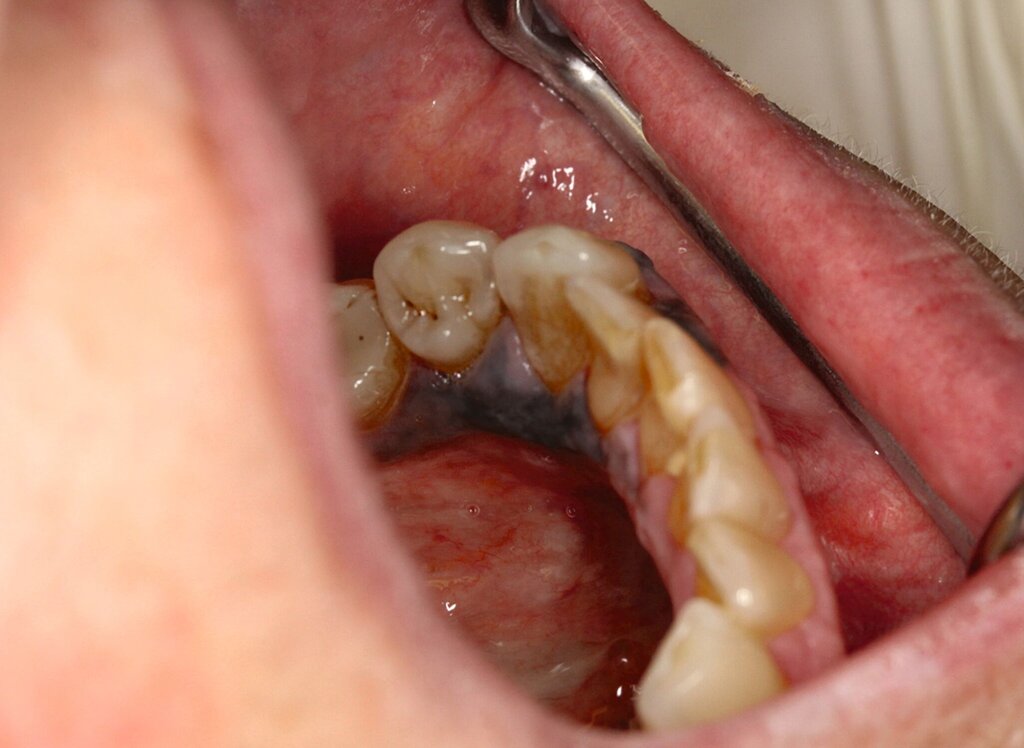

Es erfolgten eine Ausbreitungsdiagnostik mittels Ultraschall der zervikalen Lymphknoten, eine Computertomografie (CT) von Hals, Thorax und Abdomen sowie eine Magnetresonanztomografie (MRT) des Schädels. Radiologisch und sonografisch zeigten sich insbesondere in Level I A/B linksbetont suspekte Lymphknoten (Abbildung 3).

Die prothetische Versorgung der Freiendsituation im dritten Quadranten wünschte die Patientin durch ihren Hauszahnarzt. Während der Heilungsphase konnte eine Interimsprothese eingegliedert werden, die langfristig durch eine Coverdenture ersetzt werden soll.